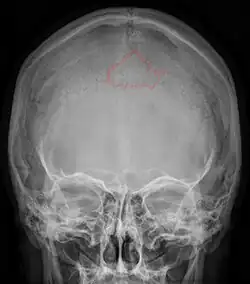

Das Inkabein oder der Inkaknochen (lat. Os incae oder Os interparietale; engl. inca bone oder incarial bone) ist am Schädel des Menschen ein akzessorischer (zusätzlicher) Knochen im Bereich der Lambdanaht (lat. Sutura lamdoidea), der Verbindung zwischen Scheitel- (Os parietale) und Hinterhauptsbein (Os occipitale). Dieser überzählige Knochen stellt eine anatomische Variation dar (Schaltknochen), die klinisch nicht relevant ist. Bei der radiologischen Befundung von Schädelaufnahmen kann sie als Nebenbefund erwähnt werden. Bei vielen anderen Wirbeltieren tritt das Os interparietale regelmäßig auf.

Wegen einer bleibenden Nahtstelle zwischen Ober- und Unterschuppe (einer persistierenden Sutura mendosa) bleibt ein einzelständiges Knochenstück der Hinterhauptschuppe bestehen. Die Form des Inkabeins ist meist dreieckig, kann aber stark variieren und auch rechteckig, Rhombus-förmig oder M-förmig sein. Sehr selten kann das Inkabein auch zwei- oder dreigeteilt sein oder noch mehr Teile enthalten (1 = Os incae totum; 2 = Os incae bipartitum; 3 = Os incae tripartitum), da manchmal weitere ein oder mehrere Längsnähte oder eine zusätzliche Quernaht existiert. Es kann den Schädelknochen in seiner ganzen Dicke umfassen, oder nur an der Außenseite oder Innenseite des Schädelknochens vorliegen.

Begrenzt wird das Inkabein vom Hinterhauptsbein, und zwar von dessen Hinterhauptsschuppe (lat. Squama occipitalis), sowie von beiden Scheitelbeinen. Die Naht zwischen dem Inkabein und Hinterhauptsbein entspricht der Sutura mendosa des Fetus. Diese Quernaht zwischen dem Inkabein und Hinterhauptsbein liegt in Höhe der obersten Linea nuchea und wird dann als Sutura occipitalis transversa bezeichnet – gewissermaßen die rechte und die linke Sutura mendosa, die in der Mittellinie verschmolzen sind.